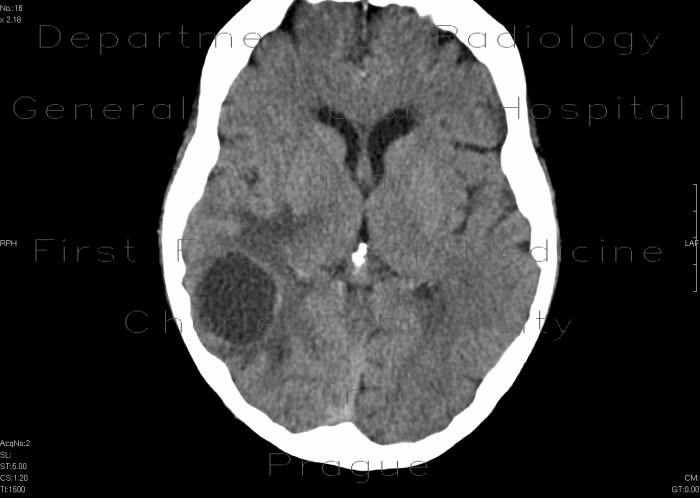

K.Okamoto et al.: CTand MR imaging of the “target sign” in metastatic brain disease 155 1a b 2a b c d Fig.1a,b. A CTscan obtained on admission. a Precontrast CT. Multiple small calcified nodules are seen at the junc-tion of gray and white matter, ... Retrieve Content

METASTASES TO THE BRAIN 4.1b. Pre-contrast Axial T1 Wtd MRI 4.1c. (E in figure A) Diagnosis: Solitary metastatic adenocarcinoma to the brain from breast primary. E 40-year old lady with a history of breast carcinoma diagnosed 6 years ago, presented with headache and ataxia. ... Retrieve Doc